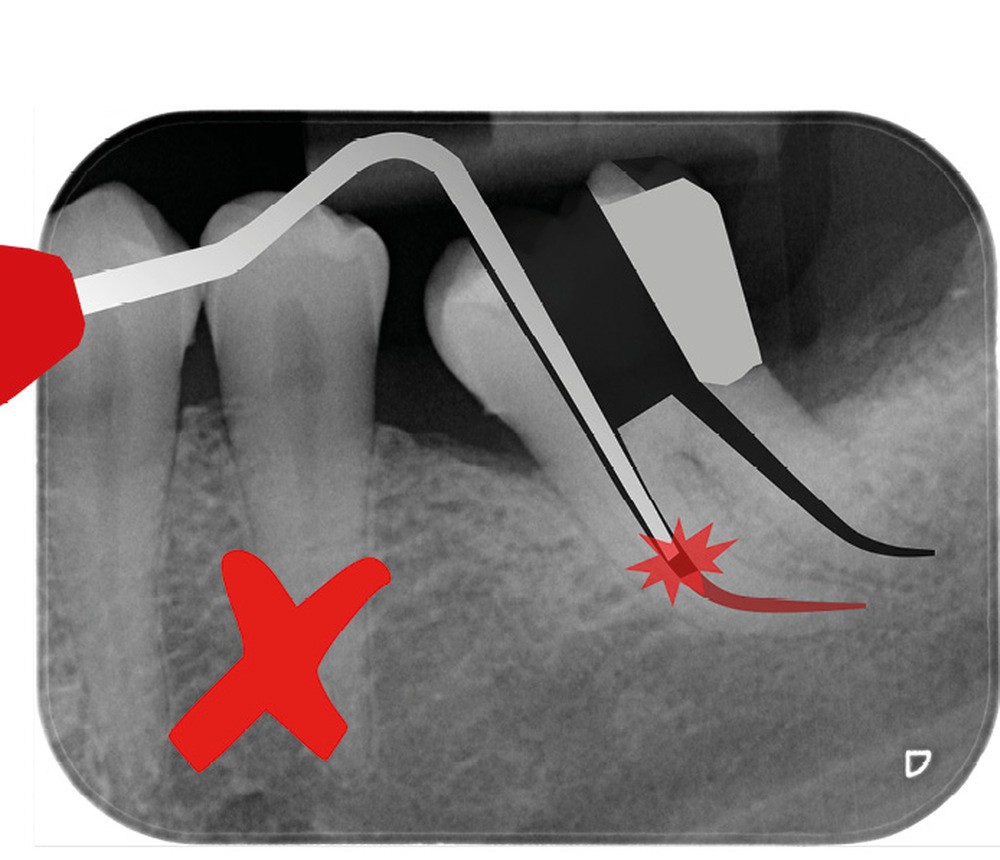

Trop large

Une cavité d’accès trop large optimiserait le pronostic endodontique mais compromettrait le pronostic biomécanique. C’est le cas de la cavité d’accès traditionnelle, qui a longtemps été « au service » du praticien réalisant le traitement canalaire (dentist-centered dentistry ou dentisterie centrée sur le praticien). Les étapes d’instrumentation, d’irrigation et d’obturation étaient ainsi facilitées grâce à des accès visuel et instrumental exagérés, aux dépens de structures dentaires saines (fig. 4).